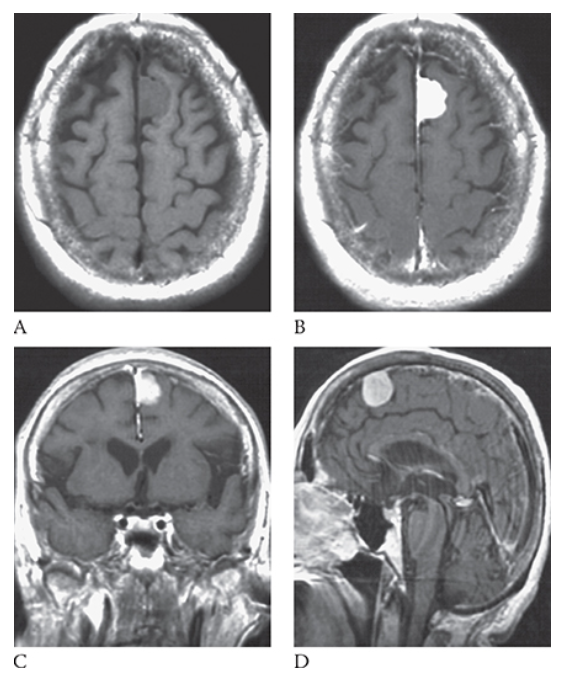

What is A

Meningioma. T1-weighted axial MR image shows an isointense left parasagittal meningioma and postcontrast T1-weighted images in the axial

What is B

Meningioma. T1-weighted axial MR image shows an isointense left parasagittal meningioma coronal

What is C

Meningioma. T1-weighted axial MR image shows an isointense left parasagittal meningioma and sagittal

What is D

Meningioma. T1-weighted axial MR image shows an isointense left parasagittal meningioma planes.